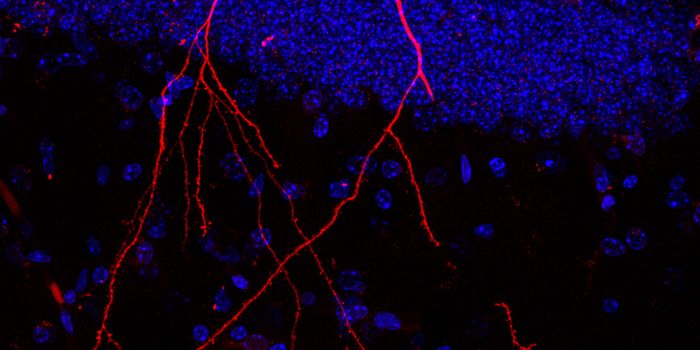

JAN 07, 2022CancerThe blood-brain barrier (BBB) describes the complex vasculature network that delivers oxygen and nutrients to the brain. ...